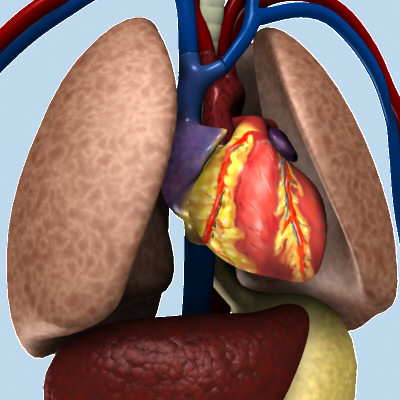

- İçki vucut azalarına zarar verir

İnsan vücudundaki en hassas ve en önemli mekanizmalar içkiden en çok etkilenen kısımlardır. İçki; sinir sistemi kütlesini, ciğerleri ve salgı bezlerini etkileyerek orada tehlikeli tahribatlar meydana getirir. İçkinin meydana getirdiği zarar daha ilk andan itibaren kendini gösterir. Yani; içki ağza ilk alındığında, dudaklara ilk dokunduğunda ve dile ilk değdiği andan itibaren başlar. Ağızdan salya akmaya, dilde kuruluk meydana gelme kendini gösterir. Hatta dil kanserine sebep olur. Aynı zamanda içki; kan damarları ve bağırsakların genişlemesine sebep olup, tehlikeli yaralar meydana getirir. Son araştırmaların tesbitine gore bağırsak kanserine yakalananların çoğu, içki tiryakisi olanlardır. Allah resulu (s.a.v) içki ile tedaviden soruldu: şöyle buyurdu: “İçki ilaç değil, bilakis hastalıktır” buyurdu. (Hadisi Müslim rivayet etmiştir).